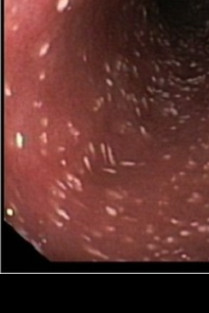

Nous proposons de renouveler et approfondir les connaissances en gastroentérologie via une approche pratique sous la forme de cas cliniques interactifs. Nous découvrirons ensemble le signalement et l’anamnèse des animaux pour développer la démarche diagnostique et les diagnostics différentiels. Les résultats des examens complémentaires seront fournis : analyses de sang, radiographies, images échographiques et endoscopiques, parfois interventions chirurgicales. C’est un échange interactif pour aboutir au diagnostic et à la discussion du traitement, tout en intégrant les mises à jour de la littérature actuelle.